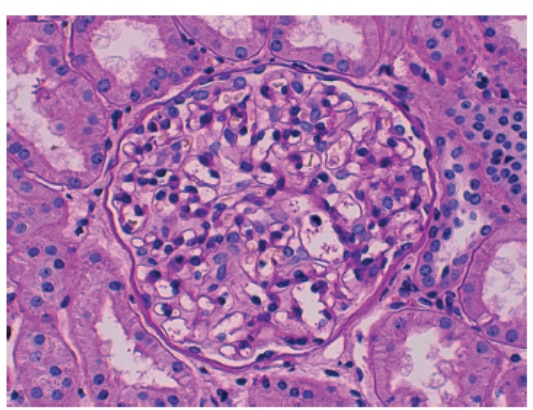

The Clinical Nephrology Section studies various kidney diseases, including membranous nephropathy and focal segmental glomerulosclerosis. The goal of our research is to better understand the evolution and outcomes of these kidney diseases and find treatments that may be more effective and less toxic.

Research Images